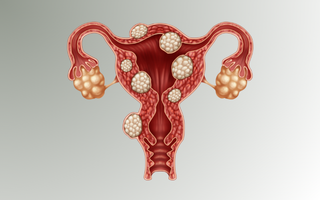

HPV Prevention & Vaccination

The clinic provides the Gardasil vaccine for protection against Human Papillomavirus (HPV), one of the leading causes of cervical cancer and other gynecologic conditions.

The vaccine offers long-term protection and is recommended for girls and women according to approved medical guidelines.